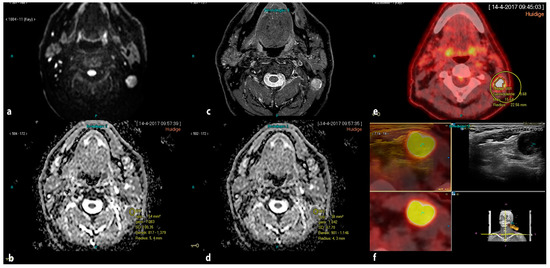

2.4. Ultrasound, Real-Time Image Fusion with FDG PET-CT and Real-Time Fused Guided FNAC